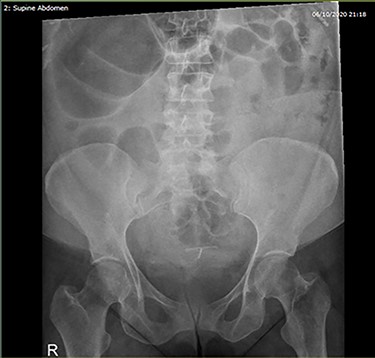

Admission blood tests were unremarkable. Abdominal X-ray showed non-specific signs of large bowel obstruction (Fig. 1). Computed tomography (CT) scan indicated unusual location of the caecum in the right upper quadrant along with gross distension up to 13 cm (Fig. 2), a whirling pattern of mesenteric vessels (Fig. 3) and a competent ileo-caecal valve. In context of her surgical history, these findings raised concern for a closed loop obstruction due to internal herniation.